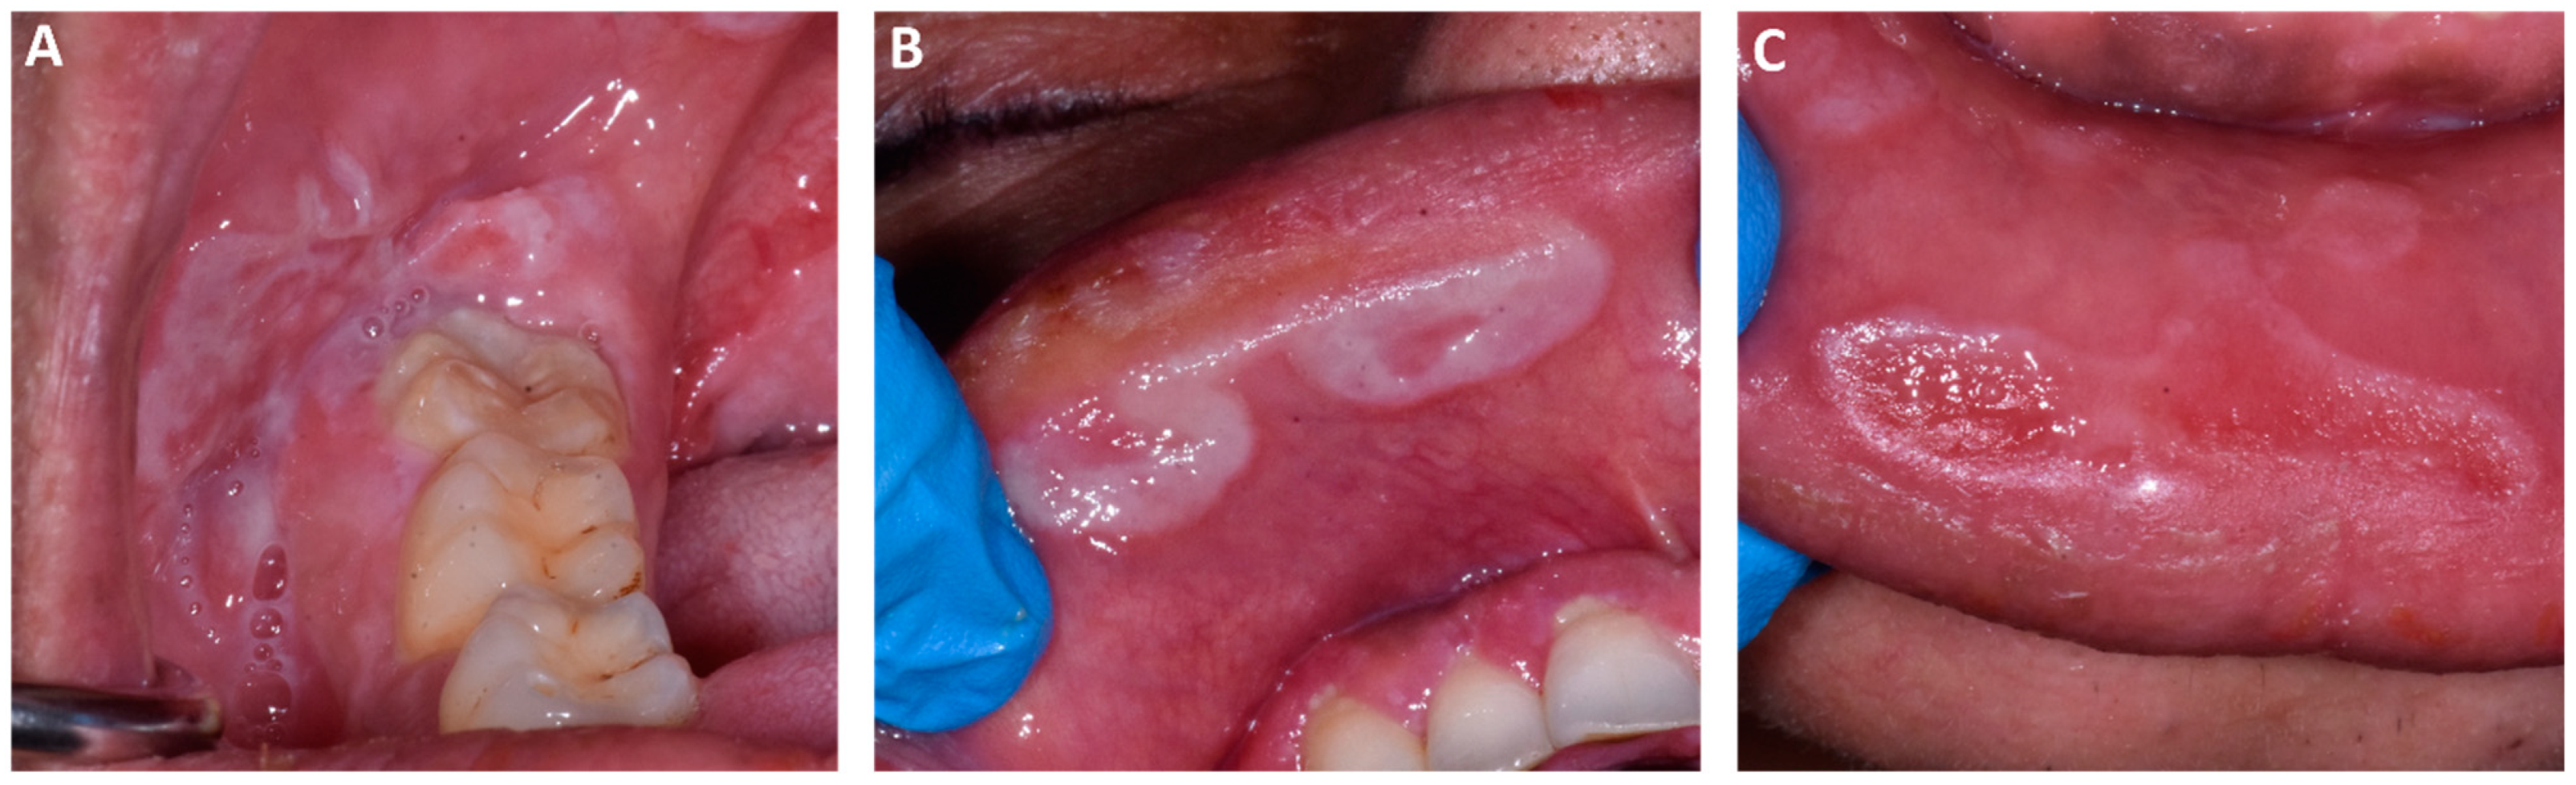

2. Case Presentation